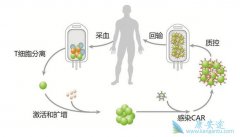

什么是 CAR-T ?CAR-T,全称是Chimeric Antigen Receptor T-Cell Immunotherapy,嵌合抗原受体T细胞免疫疗法。这是一个出现了很多年,但是近几年才被改良使用到临床上的新型细胞疗法。和其它免疫疗法类似,它的基本原理就是利用病人自身的免疫细胞来清除 ...

CAR-T 作为肿瘤免疫治疗的方法之一,以其副作用小、治疗效果显著,被称为继手术、化疗、放疗后的第四大肿瘤治疗手段,其正逐渐成为未来肿瘤治疗的新方向。但是,它也有着不可避免的副作用及技术难题。(1)实体肿瘤效果较差。目前,治疗效果最成功的当 ...